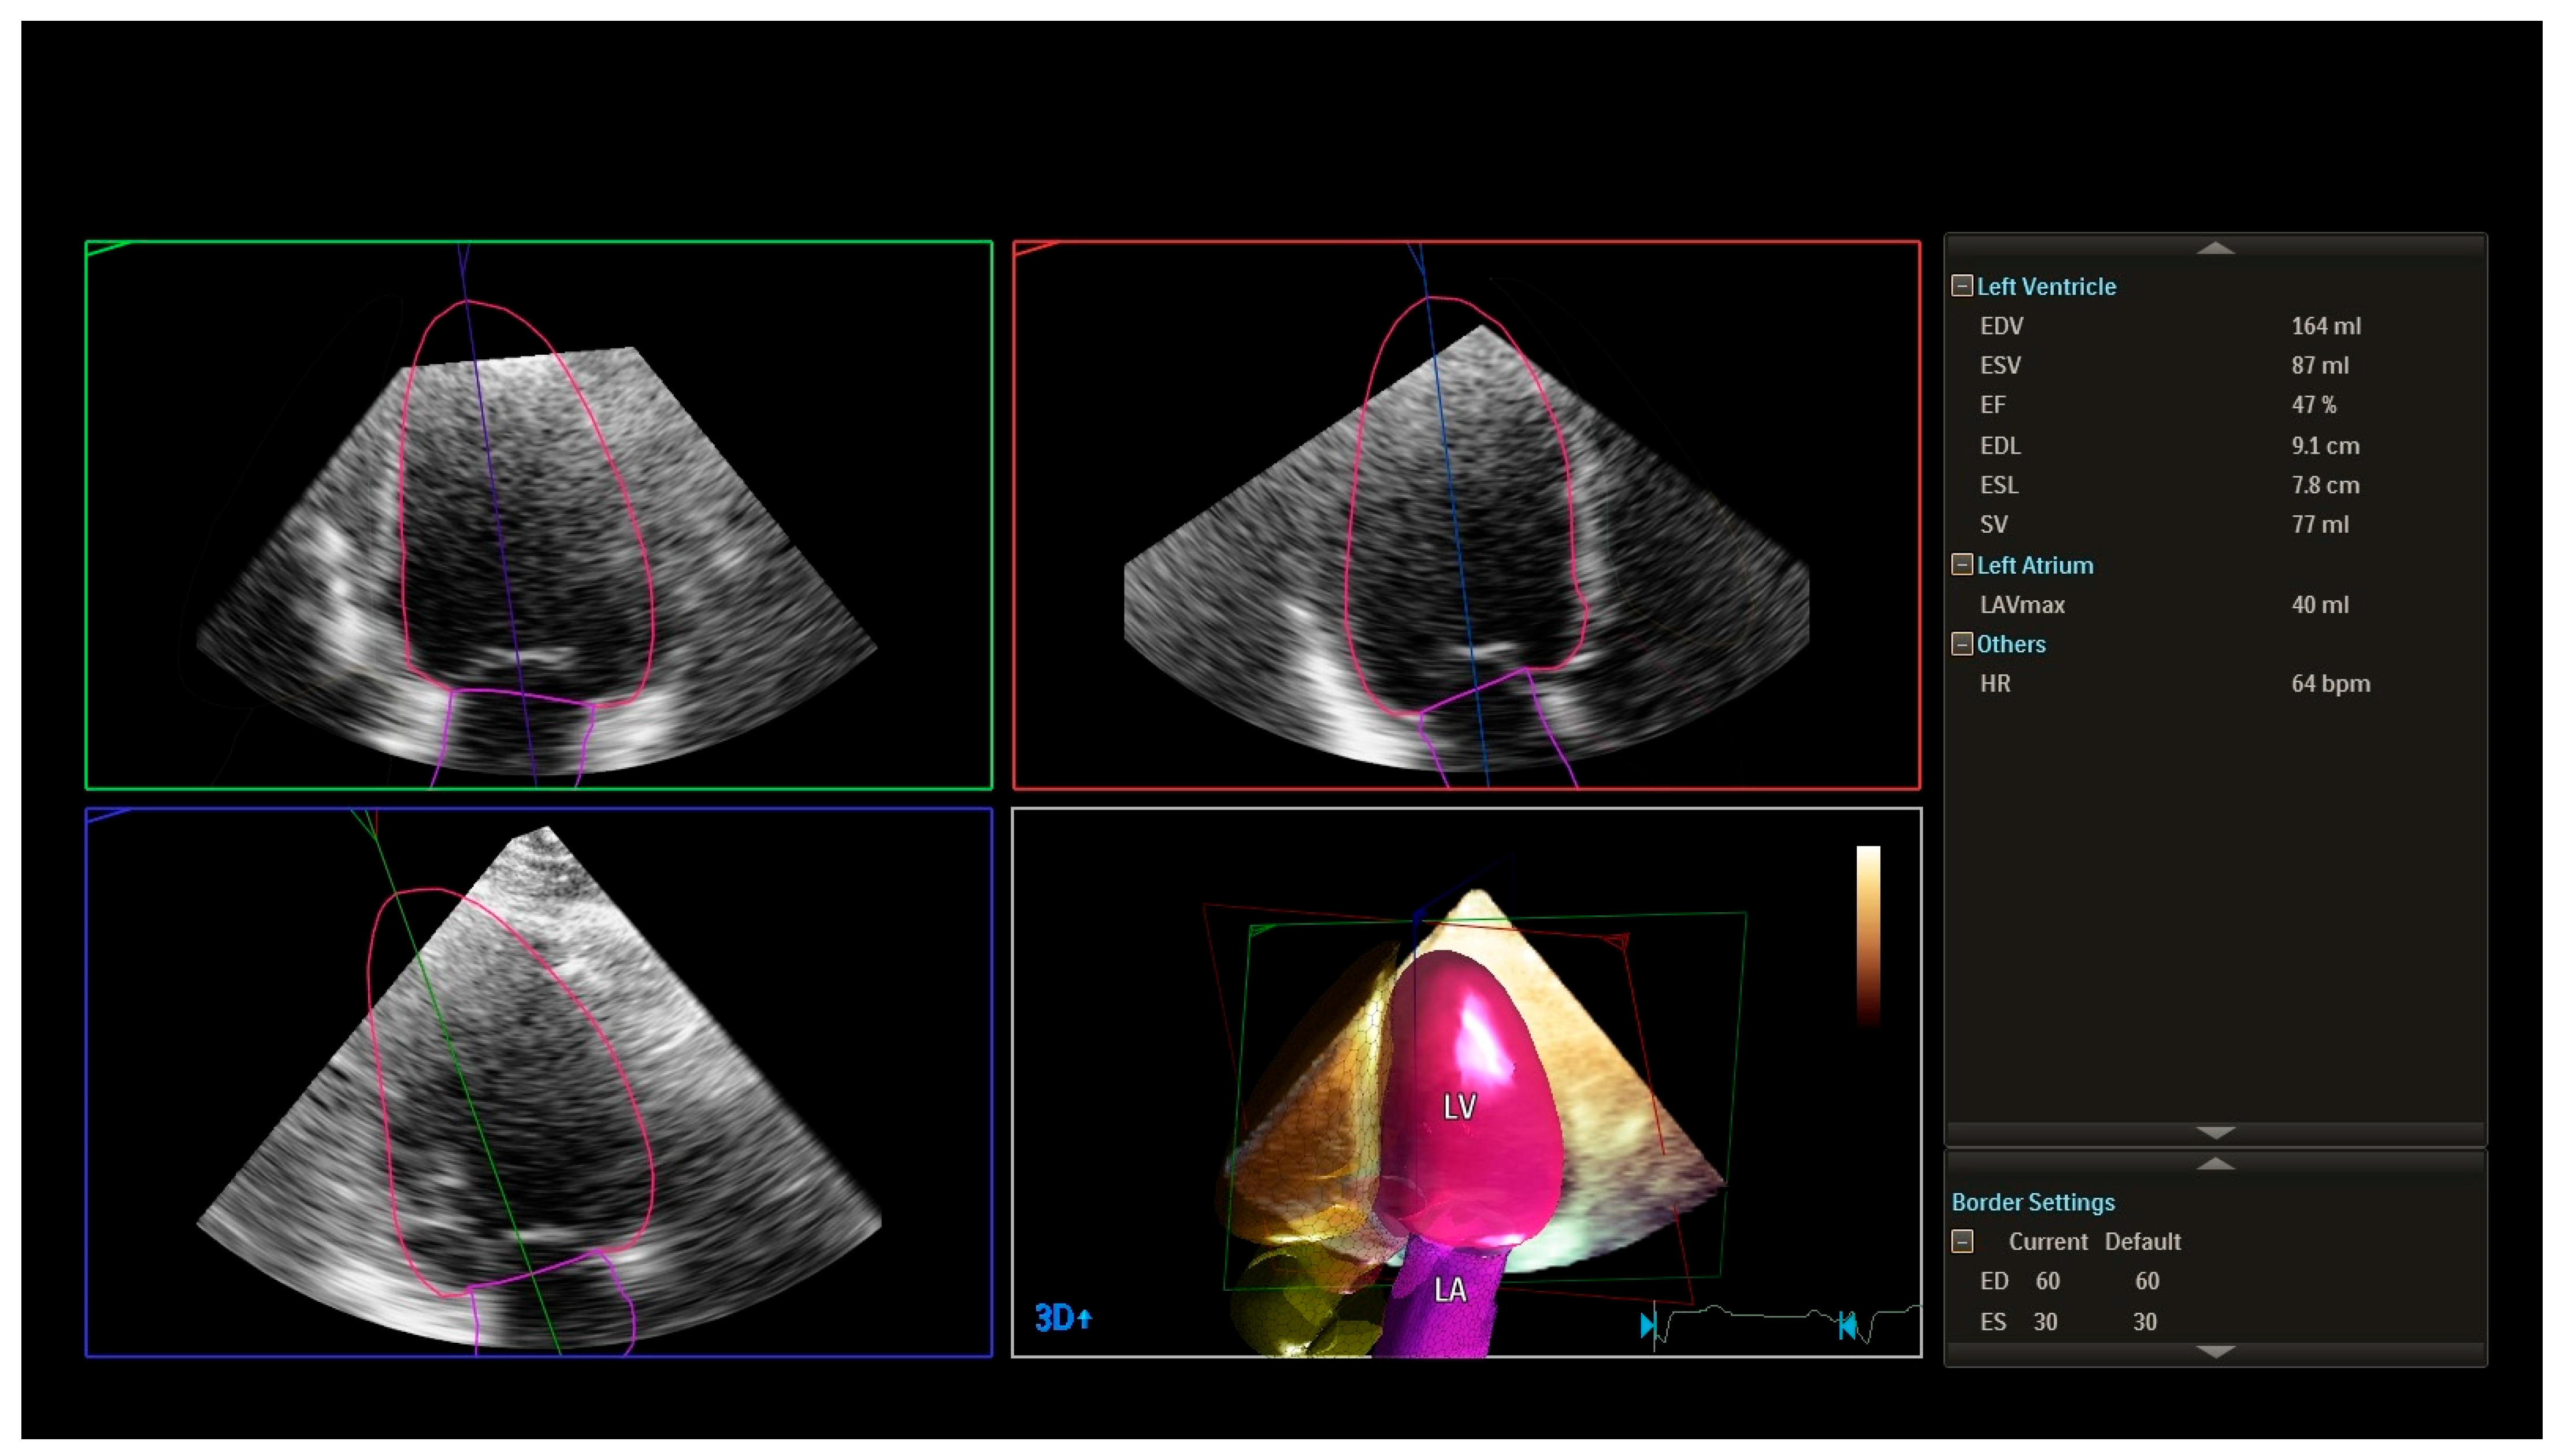

- Global longitudinal strain (GLS): Assessed by 2D speckle-tracking echocardiography using apical views (four-chamber, two-chamber, and long-axis). The endocardial border was manually traced, and tracking was automatically performed, with manual adjustments as necessary. A GLS value less negative than −19% (i.e., >−19%) was considered abnormal based on vendor-specific reference ranges.

- Philips. Bringing 3D Ultrasound into Practice for Cardiac Quantification: Philips Dynamic Heart Model; Koninklijke Philips N.V.: Singapore, 2018. [Google Scholar]

- Xing, Y.Y.; Xue, H.Y.; Ye, Y.Q. Heart Model AI three-dimensional echocardiographic evaluation of left ventricular function and parameter setting. Int. J. Gen. Med. 2021, 14, 7971–7981. [Google Scholar] [CrossRef]

- Wu, V.C.C.; Kitano, T.; Chu, P.H.; Habibi, M.; Negishi, K.; Marwick, T.H. Left ventricular volume and ejection fraction measurements by fully automated three-dimensional echocardiography left chamber quantification software versus CMR: A systematic review and meta-analysis. J. Cardiol. 2023, 81, 19–25. [Google Scholar] [CrossRef] [PubMed]

| LVEF (2D), % | 60 ± 4 | 58 ± 5 | 55 ± 6 | 52 ± 7 | <0.001 |

| LVEF (3D), % | 59 ± 5 | 57 ± 6 | 53 ± 7 | 50 ± 8 | <0.001 |